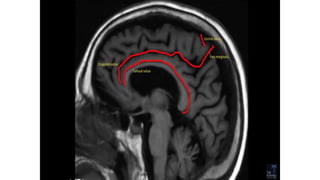

SULCI & GYRI

SULCUS IS THE DEPRESSION [VALLEYS]

AND

Fissure/sulcus Importance

• Interhemispheric fissure • Separates two lobes

 Sylvian fissure/ Lateral

Sulcus

 Frontal to temporal

 Central sulcus  Frontal to parietal

 Callosal sulcus

 Cingulate sulcus

 Interparietal sulcus

 Parieto occipital sulcus

 Calcarine sulcus

12

Yellow: cingulate gyrus; red: hippocampus; green: temporal lobe

neocortex; blue: insula, pink: uncus; P: parahippocampal gyrus